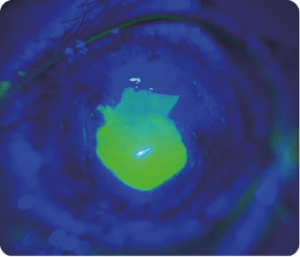

Oftalmoloji teşhisinde görüntülemenin giderek daha önemli bir rol oynadığı kabul edilmektedir. Spectrum Adaptör, özellikle ön segment görüntüleme için tasarlanmış bir akıllı telefon adaptörüdür. Optometristler, pratisyen hekimler, çocuk doktorları, veteriner hekimler vb. için temel göz muayenesi talebini karşılamak üzere 10x büyütme sağlar. Özel olarak tasarlanmış optik lens, Spectrum Adaptör’ün birinci basamak göz muayenesi ve teletıp için net ön görüntüler yakalamasını sağlar. Bu sayede, profesyonellerin etkili bir şekilde önleyici bakım ve teşhis yapmalarına olanak tanır.

Image Showcase